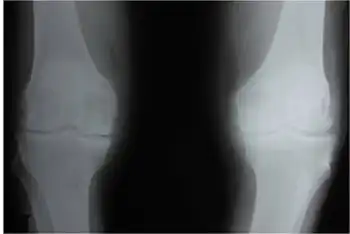

| X-ray of a knee with chondrocalcinosis | |

Chondrocalcinosis or cartilage calcification is calcification (accumulation of calcium salts) in hyaline cartilage and fibrocartilage.[1] It can be seen on radiography.

Chondrocalcinosis can be visualized on projectional radiography, CT scan, MRI, US, and nuclear medicine.[1] CT scans and MRIs show calcific masses (usually within the ligamentum flavum or joint capsule), however radiography is more successful.[1] At ultrasound, chondrocalcinosis may be depicted as echogenic foci with no acoustic shadow within the hyaline cartilage.[8] As with most conditions, chondrocalcinosis can present with similarity to other diseases such as ankylosing spondylitis and gout.[1]